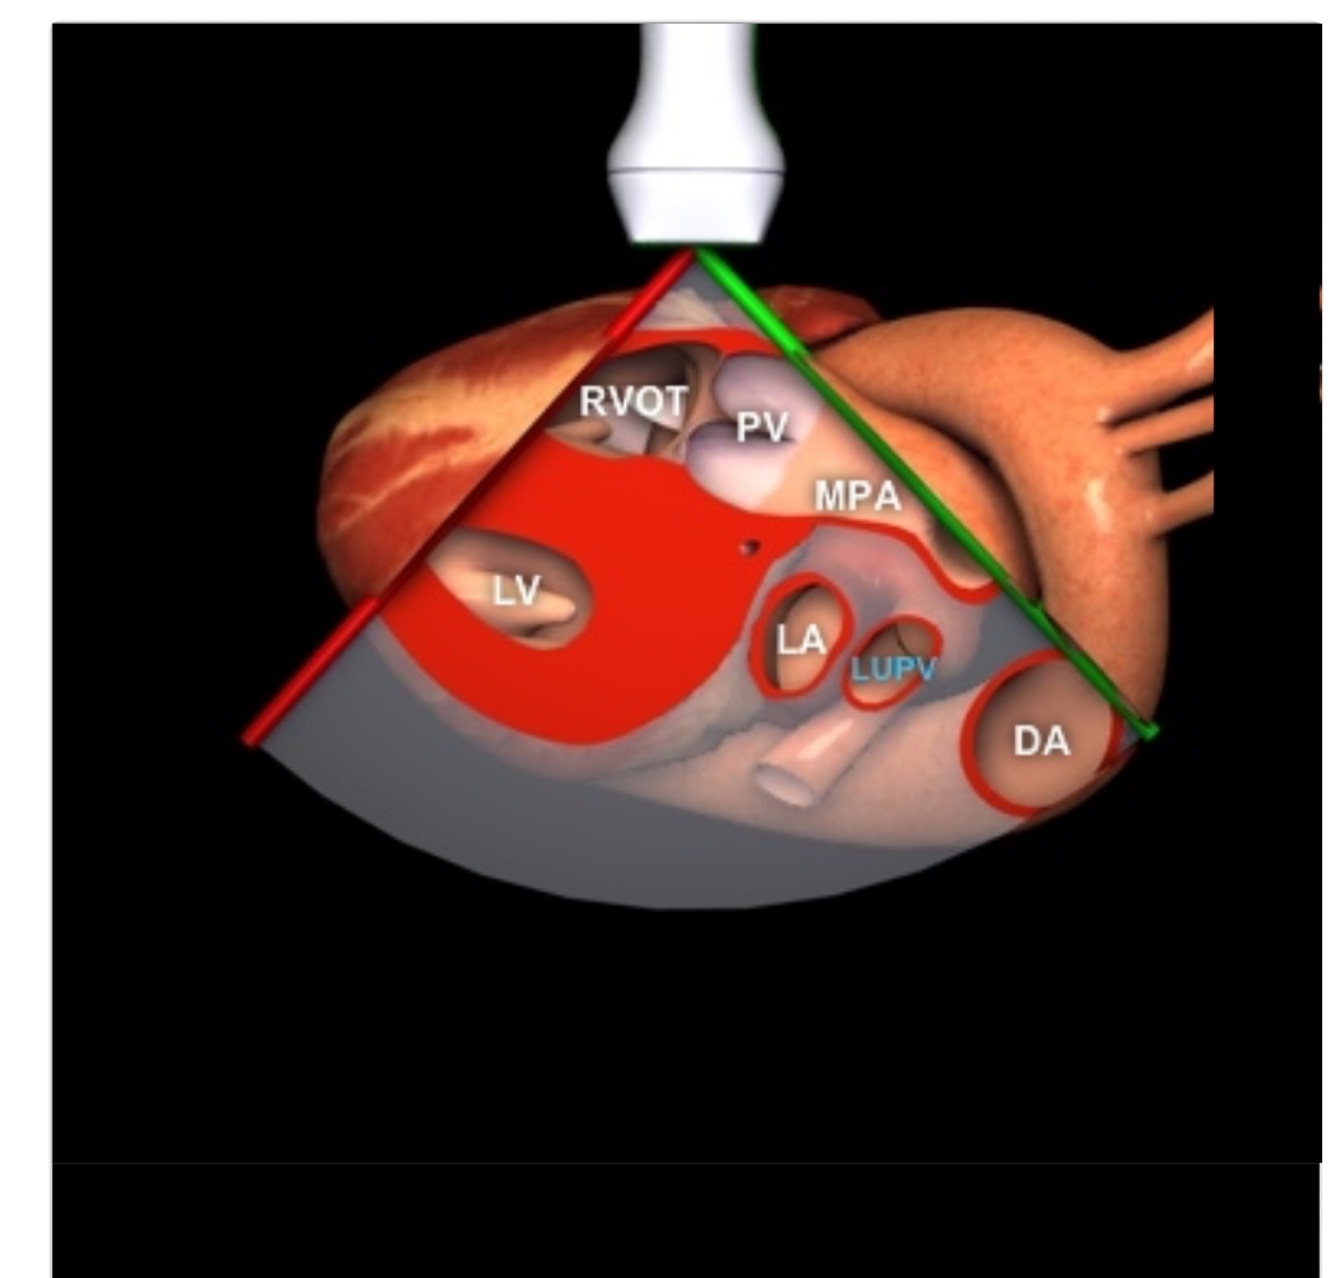

PLAX

Septum and posterior wall in true end diastole

LVOT in mid systole

Pathologies: MV prolapse, MR jet direction, MR vena contracta, AR vena contracta, pericardial effusion, pleural effusion